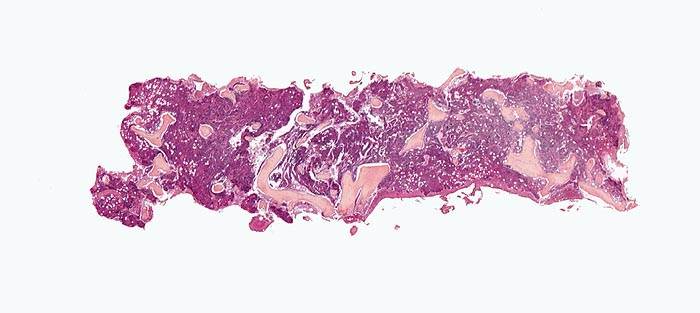

PathoPic ID 3903 - Primäre Myelofibrose (PMF)

Primäre Myelofibrose (PMF)

Knochenmark, Beckenkamm

Hyperplastisches Mark mit wechselnder Verdrängung des Fettmarks. Die Spongiosabälkchen sind diskret

verplumt und verdickt.

Splenomegalie, leichte Anämie, Leukozytose und Thrombozytose festgestellt bei einer Routineuntersuchung bei asymptomatischer Patientin.